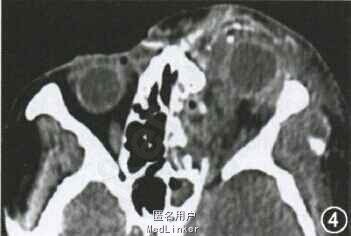

随访:术后第3天复查眼眶CT,证实左眼球基本复位,且眼环连续性良好(图4)。患者左眼球运动差,仅表现为轻度内转,外转及垂直位运动受限明显。右眼视力保持良好,无外伤并发症。手术后1周复查眼眶CT,术后左眼CT提示眼环连续性良好,眼球无明显萎缩内陷,筛窦填塞明胶海绵部分吸收,骨折断端无明显移位,眼球基本复位。 讨论:本例患者外伤后眼周组织损伤严重,眶脂肪脱位,眼球损伤主要表现为4。5 mm角巩膜缘全层裂伤,少量眼内组织脱出,因此脱位眼球复位术能得到较满意效果。本例患者由于特殊外伤位置,眼球脱位过程中角巩膜缘裂伤较重,如临床眼球壁破坏程度较轻,术后复位及视力保持机会可能会更大。 doi:10.3760/cma.j.issn.0412-4081.2015.10.018